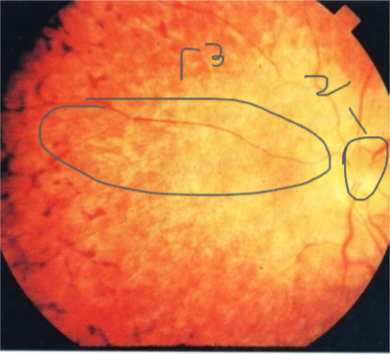

Central retinal vein occlusion

all of the following are a complication of this case EXCEPT ?

- A) ischemia

- B) Macular edema

- C) Neovascular glaucoma

- D) cataract

Wet macular age related degeneration